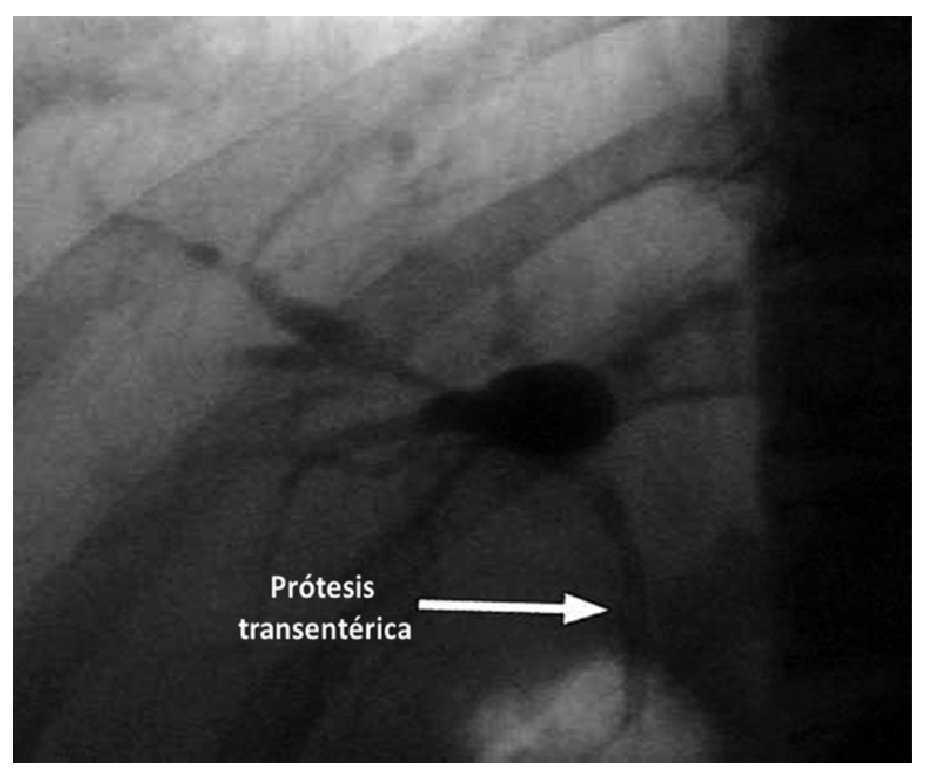

¿ Figura 3. Paso de la prótesis transduodenal con drenaje biliar.

¿ Figura 4. Colédoco dilatado por cáncer de páncreas, sin flujo al dopler A). Punción del colédoco B). Colangiograma C). Paso de la prótesis transduodenal D). Drenaje biliar con total pasage de prótesis transduodenal E). Visión endoscópica de prótesis F).